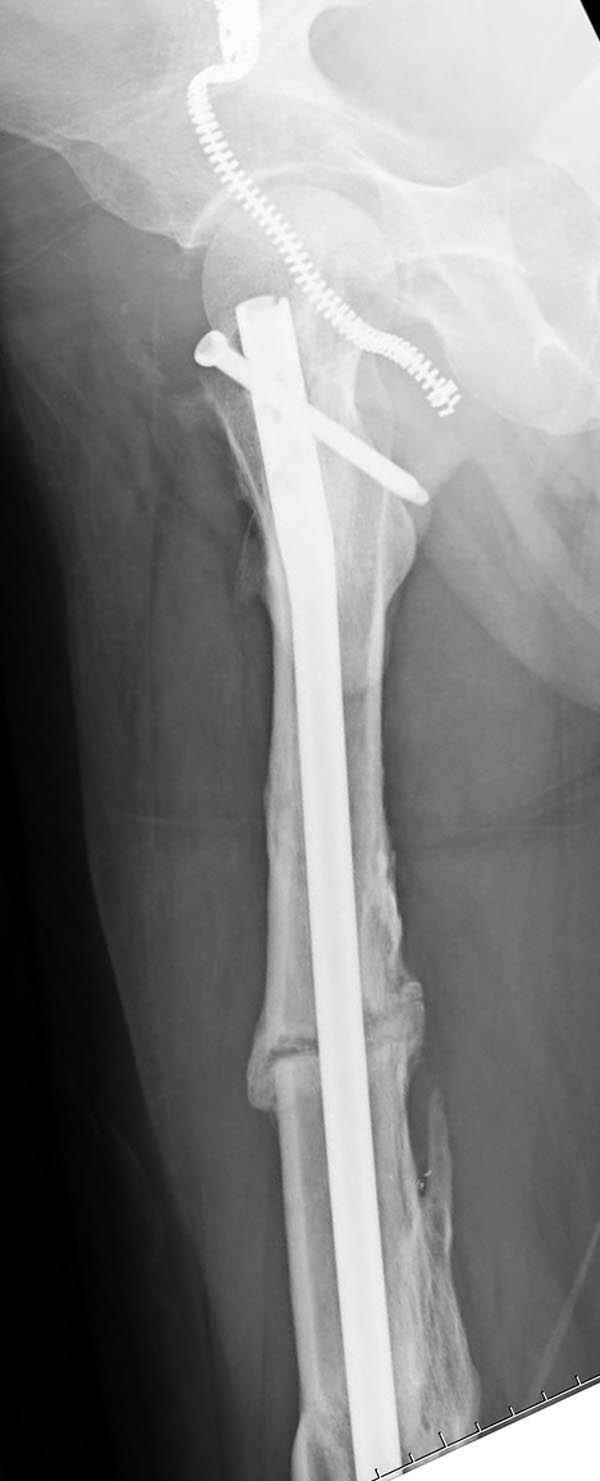

Инфекция канала и стрессовый перелом:

Представляю снимки больного с политравмой: леченного в другом мед.учреждении по поводу открытого перелома бедра, сперва аппаратом наружной фиксации, затем пластиной. Обратился к нам через 8 месяцев после удаления пластины с проблемой несросщего перелома бедренной кости, без клинических проявлении к инфицированию (не все снимки сохранены)

Рутинный интрамедуллярный остеосинтез с расверливанием и с фиксацией реконструктивным трокантерик штифтом (рис №1, №2),

если первые 4 месяца послеоперационного периода проходил без проблем, но на 5 месяце появились боли в дистальном отделе бедра и температура, т.е. симптомы медуллярного инфицирования (рис №3, №4).